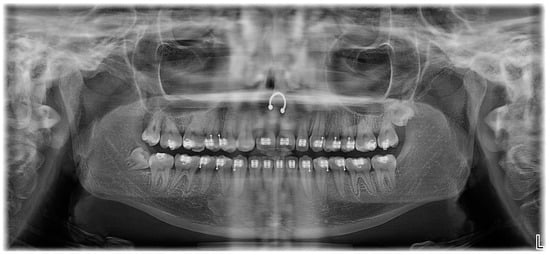

2. Case Presentation